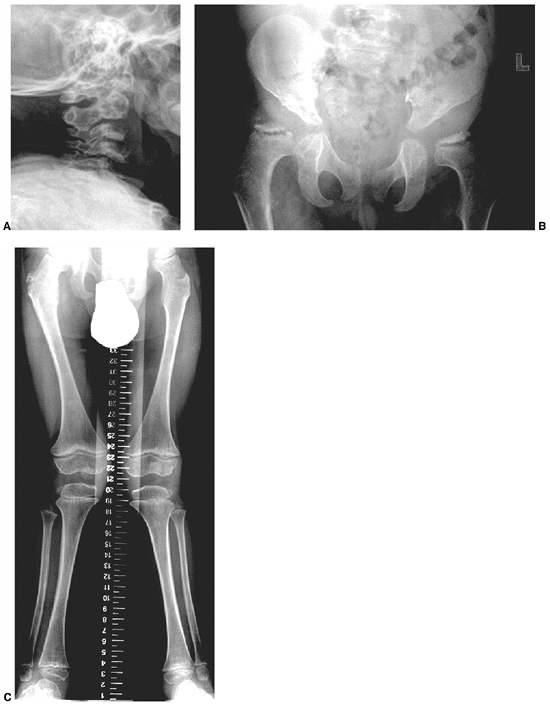

dysplastic (Fig. 9.3). The spinal deformity is

often associated with kyphosis, especially in the lumbar spine region.

Surgery is considered for rapidly progressive curves in skeletally

immature individuals, or for large progressive curves in skeletally

mature individuals. Surgery in these patients is challenging, with

higher complication rates reported than for idiopathic scoliosis.

Infection, instrumentation fixation failure, pseudarthrosis, or coronal

and sagittal curve decompensation occur in 10% to 20% of patients.

Computerized tomography (CT) scan to assess bony anatomy, especially of

the pedicles, is quite useful in preoperative planning of hook and

screw placement. Avoidance of extreme correction, extension of the

fusion to vertebrae that are neutral and stable in both planes, and

fusing both primary and secondary curves may prevent curve

decompensation, hardware failure, and pseudarthrosis. We recommend

these techniques in the operative management of this condition. Other

unusual spinal deformities can occur, such as subluxation of vertebrae (35).